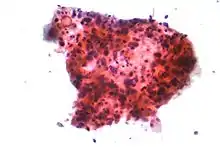

يعدّ التدخين هو السبب الأول لحالات سرطان الرئة حيث يشكل حوالي 85% كسبب رئيسي للإصابة بذلك السرطان وفقط حوالي 10-15٪ من حالات السرطان تحدث عند الأشخاص الذين لم يدخنوا أبدًا.[9][10][11][12] غالبًا ما تنتج هذه الحالات عن مجموعة من العوامل الوراثية مثل التعرض لغاز الرادون، أو الأسبستوس، أو التدخين غير المباشر، أو أشكال أخرى من تلوث الهواء. يمكن رؤية سرطان الرئة على الصور الشعاعية للصدر والتصوير المقطعي المحوسب (CT). يتم تأكيد التشخيص عن طريق الخزعة.[13]

- التشخيص المختبري بعد أخذ عينة من الورم[49]